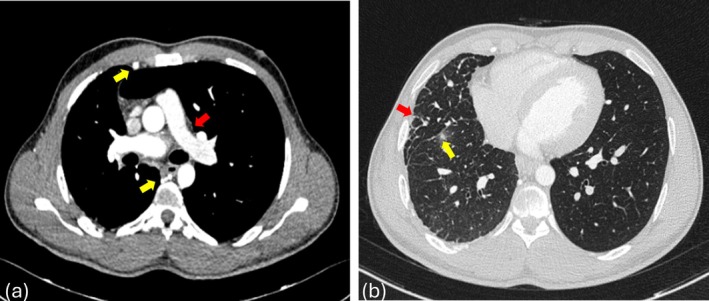

单侧肺动脉闭锁(UPAA)是一种罕见的先天性异常,其特征是缺少一条肺动脉。本文研究了三例UPAA,主要影响右侧,尽管有一例涉及左侧。常见的特征包括咯血,在两例患者中观察到,一例有慢性病史,需要栓塞,另一例是轻微的,最近发病。第三例是在术前评估时偶然发现的。所有病例均表现出不同程度的同侧肺体积缩小和相关间质改变或纤维化。UPAA可无症状或以咯血、反复感染或呼吸困难为表现。诊断依赖于计算机断层肺血管造影(CTPA)或磁共振血管造影(MR)。治疗方法从观察到栓塞或严重病例的全肺切除术。死亡率约为7%,肺动脉高压和出血是主要的预后因素。

Unilateral pulmonary artery atresia (UPAA) is a rare congenital anomaly marked by the absence of one of the pulmonary arteries. This article examines three instances of UPAA, predominantly affecting the right side, although one case involved the left side. Common characteristics included hemoptysis, observed in two patients-one with a chronic history necessitating embolization and another with a mild, recent onset. The third case was identified incidentally during a preoperative evaluation. All cases demonstrated varying degrees of ipsilateral lung volume reduction and associated interstitial changes or fibrosis. UPAA can be asymptomatic or present with hemoptysis, recurrent infections, or breathlessness. Diagnosis relies on computed tomography pulmonary angiography (CTPA) or magnetic resonance (MR) angiography. Management ranges from observation to embolization or pneumonectomy in severe cases. Mortality is around 7%, with pulmonary hypertension and haemorrhage being major prognostic factors.